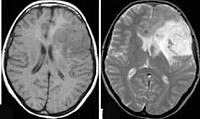

Наилучшими способами объективного выявления опухоли полушарий мозга признаны методы нейровизуализации: КТ и МРТ головного мозга. Они позволяют определить точную локализацию опухоли полушарий мозга и дифференцировать ее от внутримозговой гематомы, кисты при сирингомиелии, абсцесса головного мозга, рассеянного склероза, эпилепсии. Однако поставить достоверный диагноз и верифицировать опухоли полушарий мозга позволяет лишь гистологическое исследование. Оно может проводится с образцами мозговой ткани, полученными в ходе стереотаксической биопсии или интраоперационно.